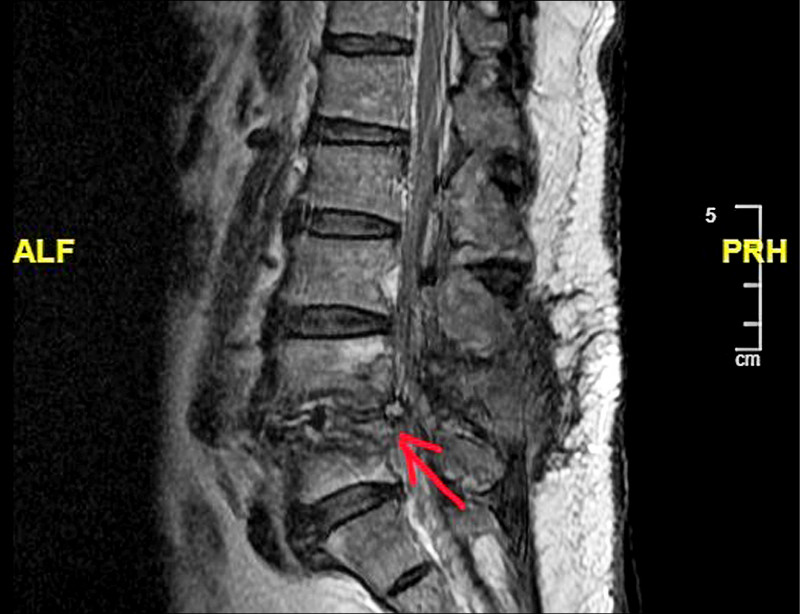

因為前述症狀,前來林口長庚醫院脊椎科門診。先幫他安排脊椎X光檢查,可以看到之前手術的釘子有鬆脫的情形(圖1),同時人工椎間盤墊片有向後外側滑脫的情形(圖2)。後續幫吳先生安排腰椎核磁共振(圖3),發現人工椎間盤墊片有向後壓到神經。吳先生的症狀和影像上的發現是相符的,因此向他解釋後續治療的方向。